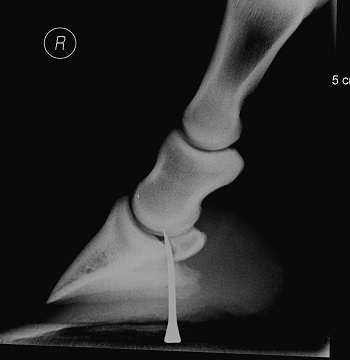

Depending on the location, your vet will usually take X-rays or scans to check the depth and which structures are affected.

Penetration injury caused by a nail through the sole of the hoof.

Photo Credit: Neil Townsend MSc BVSc MRCVS, Three Counties Equine Hospital